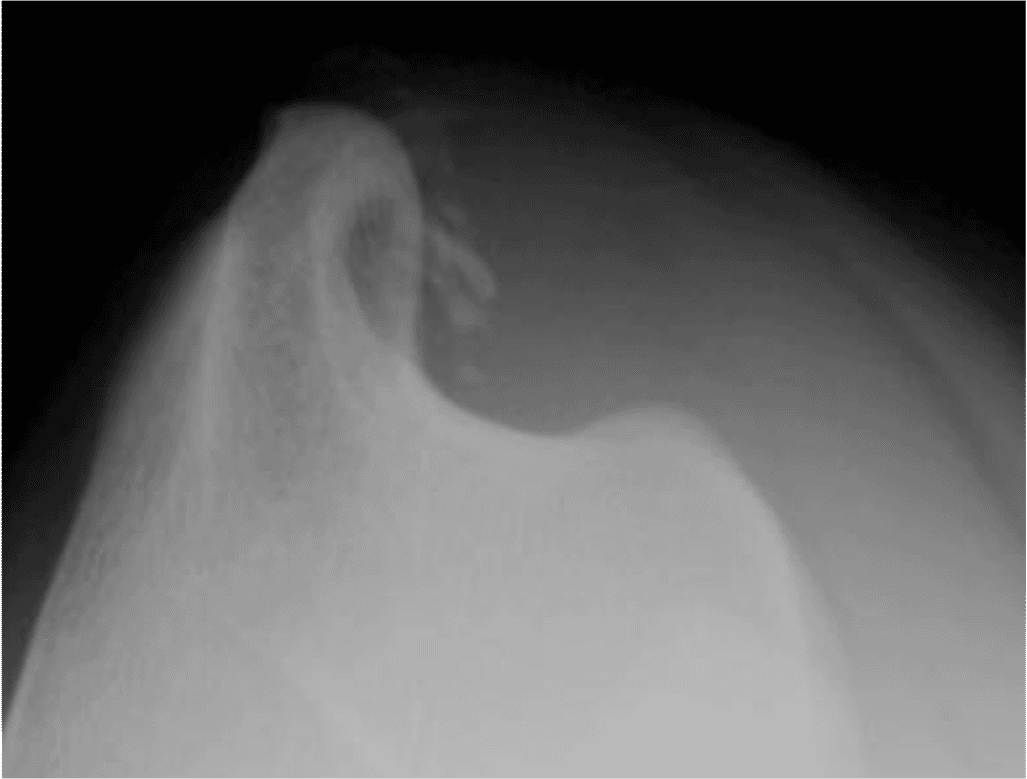

La douleur associée à l'insertion du tendon sus-épineux (le plus souvent à la jonction musculo-tendineuse) est une cause fréquente de boiterie non diagnostiquée du membre thoracique, en particulier chez les chiens sportifs. Comme pour les lésions de l'iliopsoas dans le membre pelvien, la boiterie est souvent insensible au repos et aux AINS et s'aggrave après un exercice intense. Le supra-épineux prend naissance dans la fosse supra-épineuse de l'omoplate et s'insère sur le tubercule supérieur de l'humérus. Il produit l'extension de l'épaule et l'avancement du membre et on pense que les lésions sont dues à des blessures répétitives. On l'observe fréquemment chez les chiens de flyball qui frappent de façon répétée la boîte avec un membre tendu. Les chiens cliniquement atteints présentent généralement une gêne à la palpation digitale ferme du tubercule supérieur au niveau du site de la lésion, l'épaule étant maintenue en flexion. La radiographie et la tomodensitométrie peuvent révéler une minéralisation dans le tendon (Figure 5) ; cependant, cette minéralisation est souvent accessoire et ne provoque généralement la douleur qu'en provoquant un conflit avec le tendon d'insertion adjacent du muscle biceps (Figure 6).